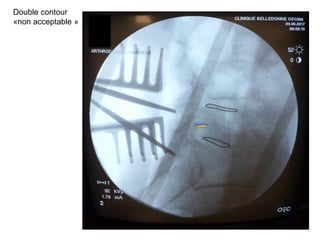

Double contour

Positionnement de l’ampli

clichés de profil

«non acceptable »